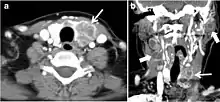

Fig. 11. Thyroid non-Hodgkin's large B-cell lymphoma in a 66-year-old female patient. an Axial enhanced neck CT scan demonstrates left thyroid lobe and isthmus homogeneously hypodense and minimally enhancing mass (white arrows). This lesion invades the prevertebral muscles (black arrows). Note the multiple enlarged level V lymph nodes (white arrowheads). b Post-treatment image shows significant reduction in size and mass effect of the left thyroid infiltrative mass, with almost complete resolution of the left cervical lymphadenopathy.[1]

Fig. 12. Diffuse thyroid large B-cell lymphoma in a 79-year-old female patient. an Axial enhanced neck CT scan demonstrates a homogeneously hypodense and minimally enhancing large right thyroid solid mass (long white arrow) extending into the thyroid isthmus. It is encasing the right carotid artery (short white arrow) and displacing of the trachea and oesophagus to the left side.[1]